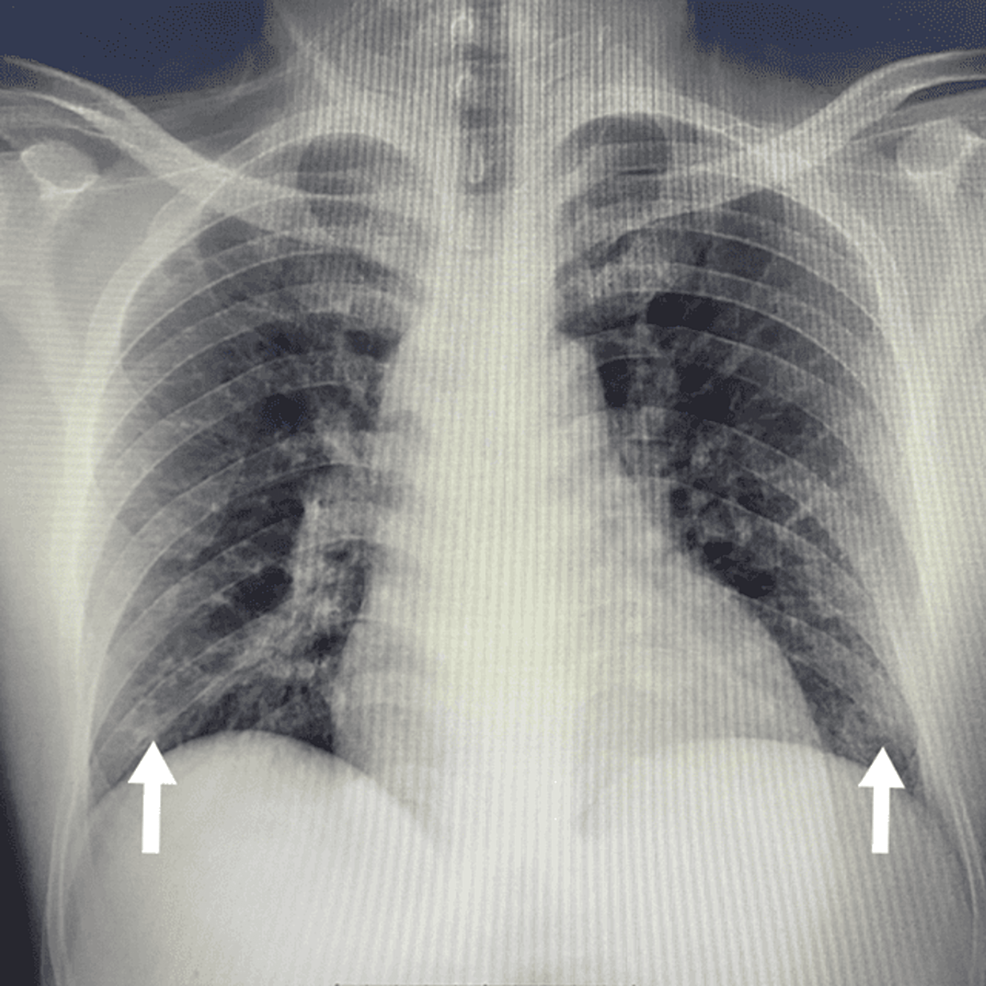

pfo shortness of breath sale